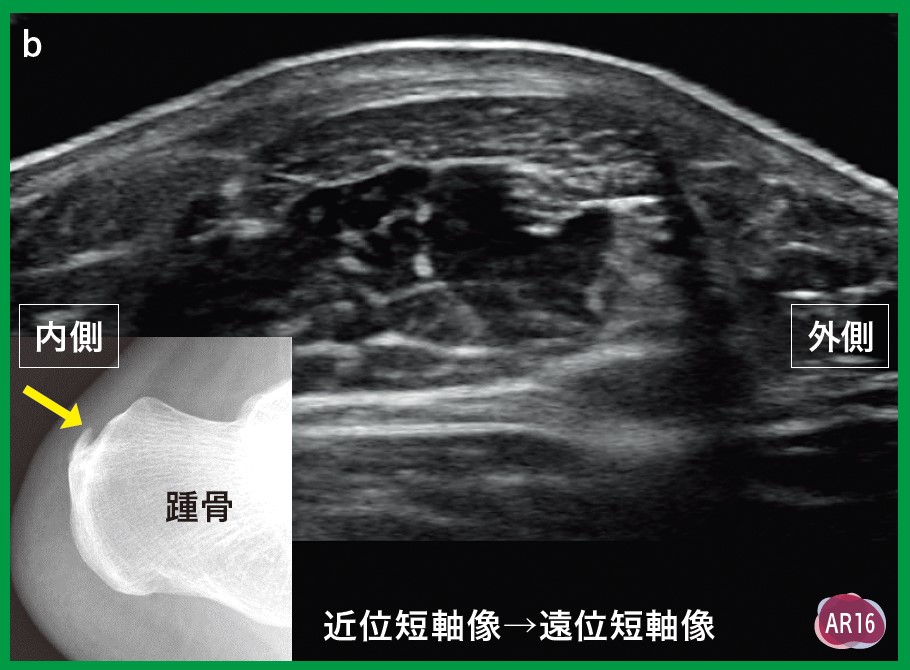

運動器エコーのメタ診断書き込みなどはなく綺麗だと思います。| カテゴリー: | 本・雑誌・漫画>>>本>>>健康・医学 |